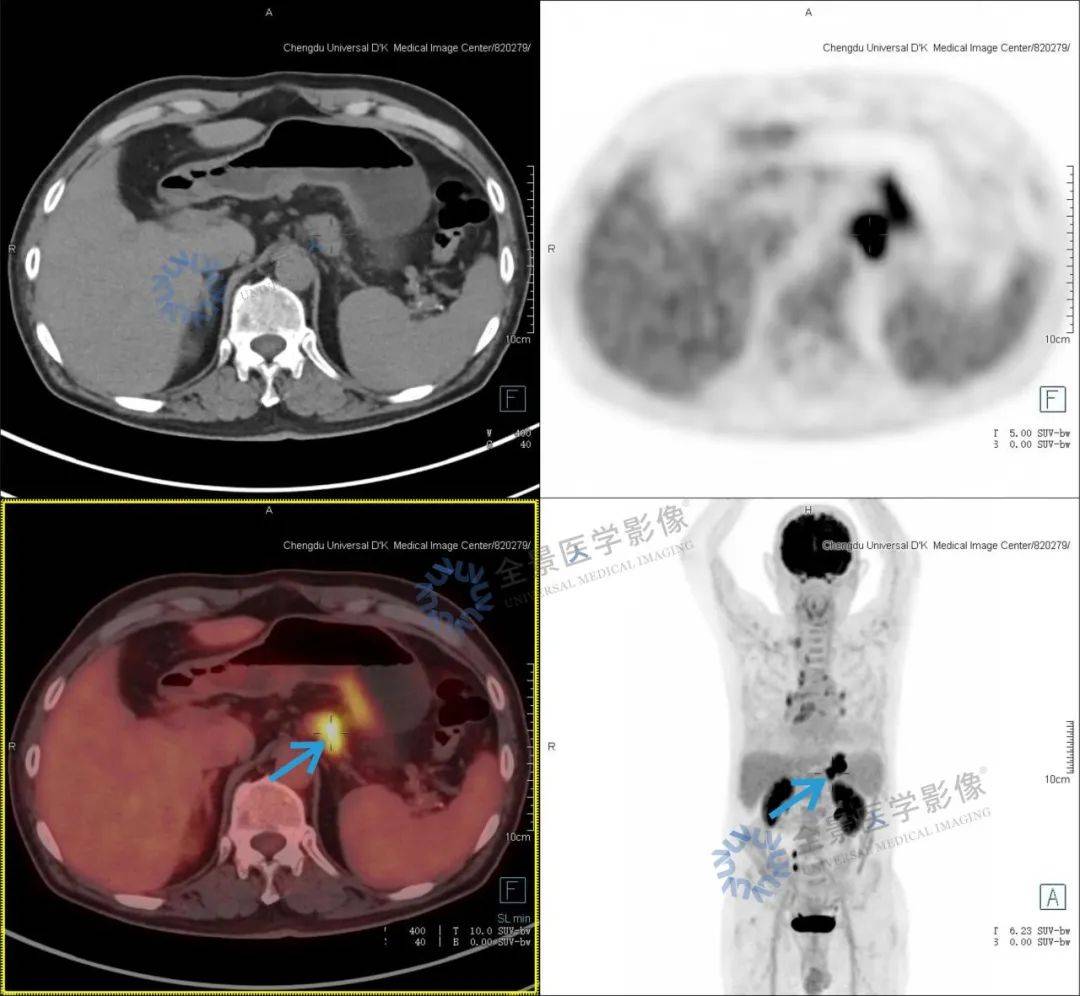

晚期胃癌病灶完全消失,双特异性抗体临床试验效果惊人

图片尺寸558x416